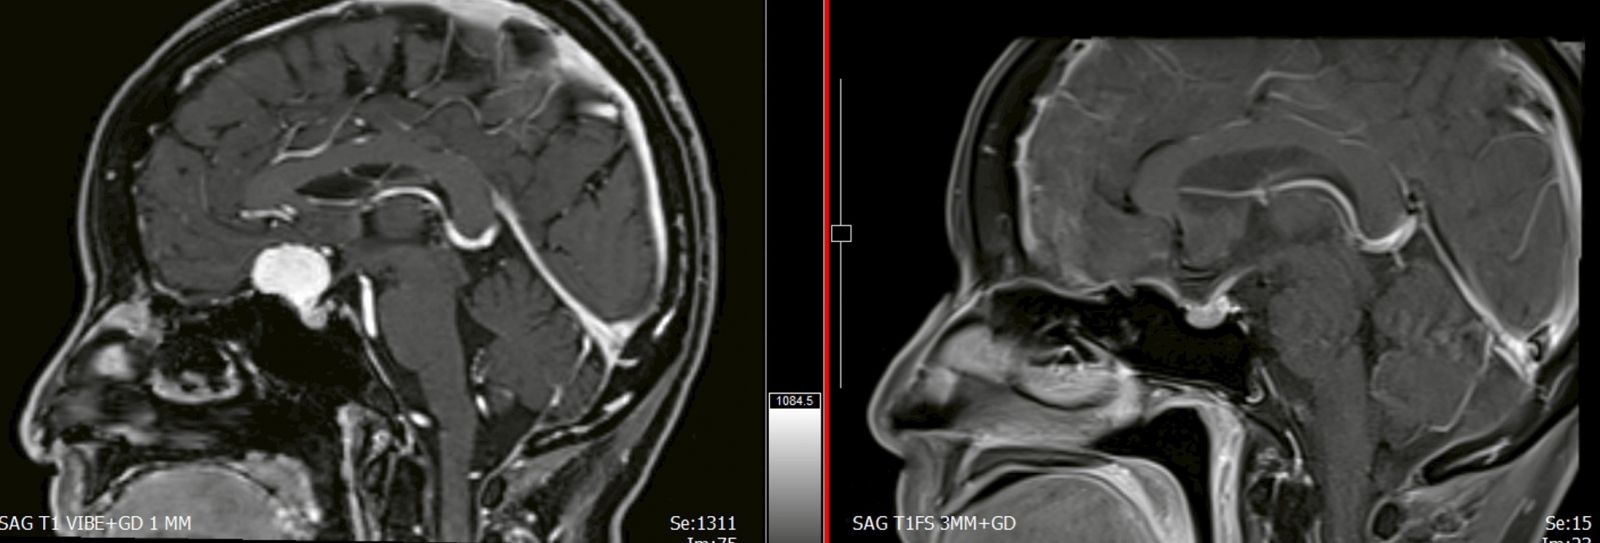

กรุงเทพมหานคร – โรงพยาบาลจุฬาภรณ์ ประกาศความสำเร็จอีกขั้นทางการแพทย์ หลังทีมศัลยแพทย์ระบบประสาทประสบความสำเร็จในการผ่าตัดเนื้องอกในสมองด้วยเทคนิค “แผลเล็กผ่านคิ้ว” (Eyebrow Keyhole Approach) ช่วยให้ผู้ป่วยไม่ต้องรับการผ่าตัดเปิดกะโหลกศีรษะขนาดใหญ่ ลดภาวะแทรกซ้อน และสามารถกลับไปใช้ชีวิตตามปกติได้อย่างรวดเร็ว

นพ.จอนาตัน อรัญ ตั้งศรีวิมล ศัลยแพทย์ระบบประสาท โรงพยาบาลจุฬาภรณ์ เป็นผู้ดำเนินการผ่าตัดเนื้องอกบริเวณฐานกะโหลกส่วนหน้า โดยใช้เทคนิคการผ่าตัดแบบแผลขนาดเล็กที่มีความแม่นยำสูง ซึ่งถือเป็นเทคโนโลยีสมัยใหม่ที่ยกระดับมาตรฐานการรักษาโรคทางสมองในประเทศไทย

จากผลการรักษาพบว่า การผ่าตัดเป็นไปอย่างราบรื่น แพทย์สามารถนำเนื้องอกออกได้สำเร็จทั้งหมด โดยผู้ป่วยมีระยะเวลาพักฟื้นในโรงพยาบาลสั้นลง และฟื้นตัวได้เป็นอย่างดีเมื่อเทียบกับการผ่าตัดแบบเปิดกะโหลกศีรษะแบบเดิม